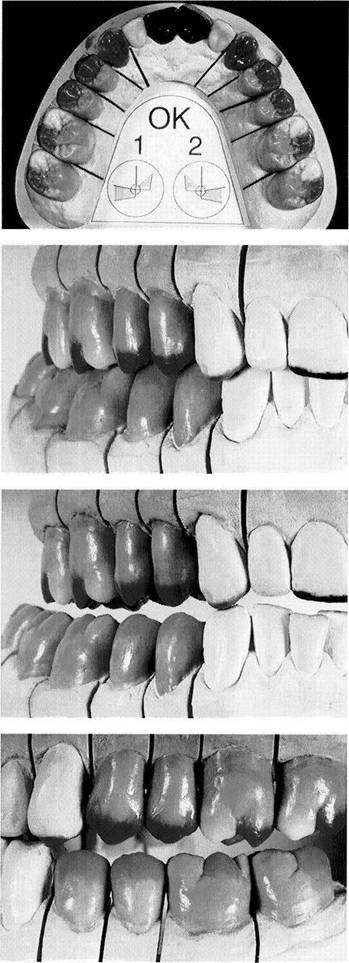

Segmented casts are used primarily to provide removable dies for the fabrication of fixed prostheses. However, they are also useful for making a detailed analysis of a patient's static and dynamic occlusal relationships. For one thing, the removal of an entire quadrant improves the view of the occlusion in the other portions of the arch. For another, by removing only those teeth that carry the current premature occlusal contacts, the effects of making occlusal changes within their space can be anticipated (see p. 236).

Various procedures have been recommended for producing a segmented cast. In addition to the classic method that uses special die pins as described on this page, another interesting method worthy of mention is the Model-Tray procedure. This uses a base-forming tray that can be disas­sembled and that has numerous orientation grooves on its inner surface (Model-Tray by Model-Tray GmbH). After the cast has been removed and sawed into sections it can be accurately reassembled in the tray.

segments for occlusal diagnosis

Although in some cases, segment­ed casts with one anterior segment and two posterior segments are ad­equate for a quick occlusal diagno­sis (left), it is preferable to prepare casts in which each posterior tooth and at least the canines can be re­moved separately.